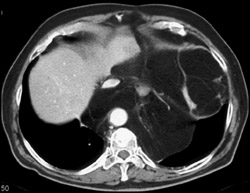

Diagnosis

Abscess Behind Knee